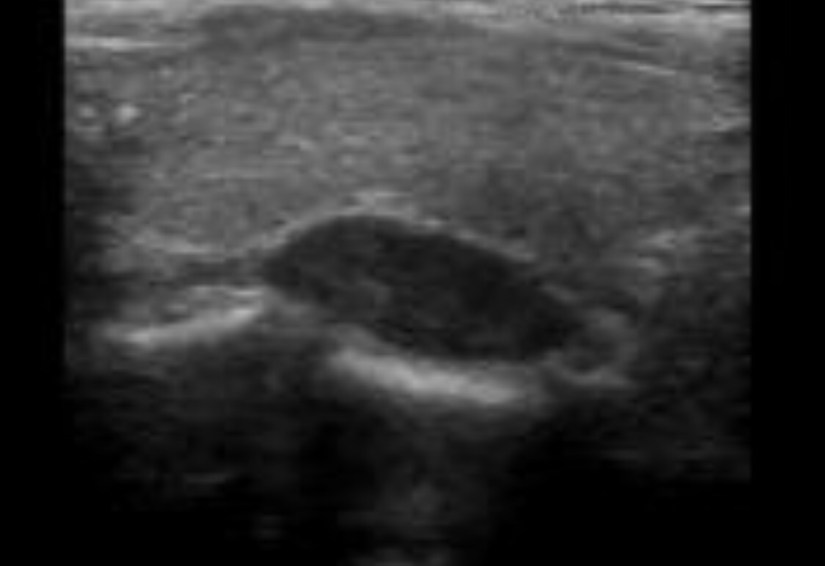

👉Ultrasonido de cuello es complementaria a la exploración de sestamibi para la localización paratiroidea y también puede identificar los nódulos tiroideos que necesitan un manejo concurrente.